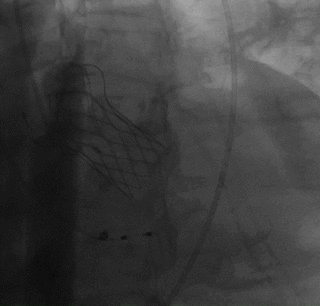

球囊预扩,确认冠脉风险

瓣膜释放至1/2

球囊后扩